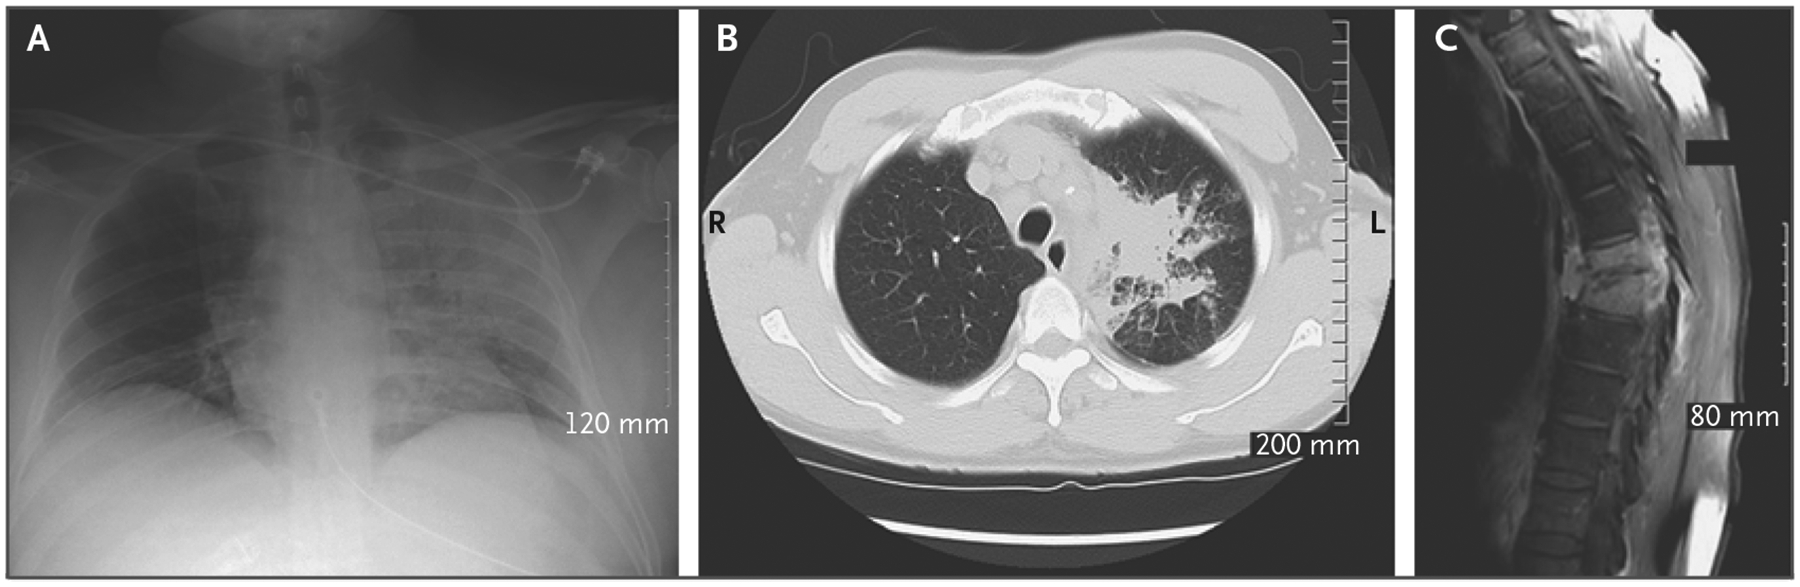

Description:Melioidosis, caused by |, is a rare but potentially fatal bacterial disease endemic to tropical and subtropical regions worldwide. It is typically acquired through contact with contaminated soil or fresh water. Before this investigation, | was not known to have been isolated from the environment in the continental United States. Here, we report on three patients living in the same Mississippi Gulf Coast county who presented with melioidosis within a 3-year period. They were infected by the same Western Hemisphere | strain that was discovered in three environmental samples collected from the property of one of the patients. These findings indicate local acquisition of melioidosis from the environment in the Mississippi Gulf Coast region.